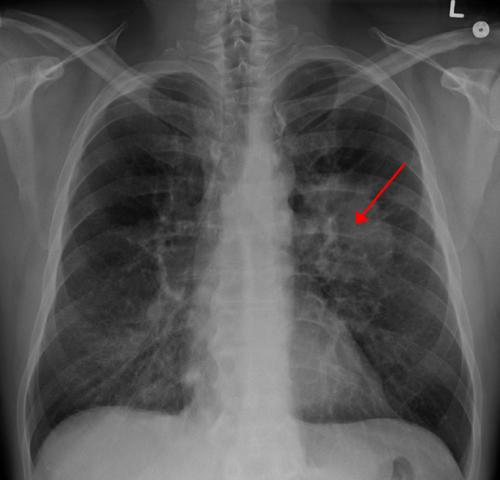

第一项研究涉及SCLC,它是一种与吸烟关联较大的肺癌。60%到70%之间的患者被确诊时已经是癌症晚期。该疾病将在一半以上的患者中传播到大脑。

第二项研究(简报162)侧重于NSCLC,其是肺癌的最普遍形式。在NSCLC肿瘤中有多个已知的基因突变,其中每个以不同的方式影响治疗。该想法是确定已发生的特定遗传变化--称为驱动程序。然后使用*制剂抑**药物精确靶向突变,而不是使用一般化疗。